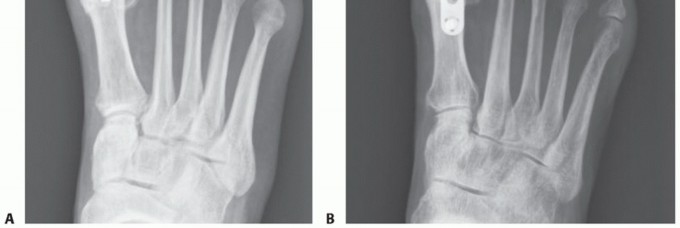

In its early stages, articular cartilage loss is present along the dorsal aspect of the first metatarsal head. As the condition progresses, articular cartilage loss extends to the central aspects of the metatarsal head and lastly the plantar aspect (FIG 2).

FIG 2 • A-C. Varying degrees of articular cartilage loss of the first metatarsal head in hallux rigidus. Radiographic findings often underestimate the extent of disease seen intraoperatively.